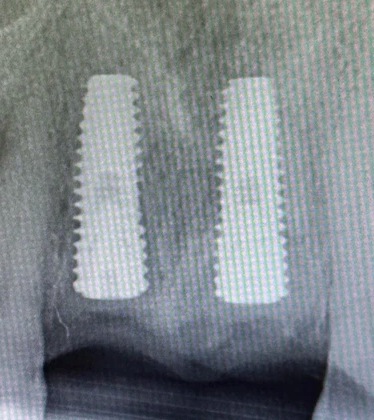

Trauma Rehabilitation with Anterior Upper Dental Implants Following Traumatic Teeth Loss

A 21-year-old patient presented after a traumatic accident resulting in the loss of both upper central incisors. Due to the extent of structural damage and the patient’s age and aesthetic expectations, implant-based rehabilitation was chosen as the definitive solution.

Two implants were placed in the anterior maxilla with precise three-dimensional positioning to support long-term bone stability and optimal aesthetic outcomes. Particular attention was given to soft-tissue management and wound closure to preserve gingival architecture in the aesthetic zone, as demonstrated by stable peri-implant tissues during healing.

A provisional restoration was provided during osseointegration to maintain appearance, phonetics, and patient confidence while allowing undisturbed healing. Radiographic evaluation confirmed correct implant angulation and depth, forming a solid foundation for the final restorations.